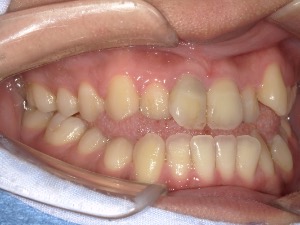

before

患者さんの年齢 20代 女性 症状 見た目が良くなりたい 治療内容 マウスピース矯正治療 費用 90万(税抜) 治療期間・回数 治療期間2年半、通院回数20回 メリット スマイルラインが綺麗 デメリット・リスク 期間がかかることがある 患者さまの声 見た目が綺麗になった - マウスピース矯正